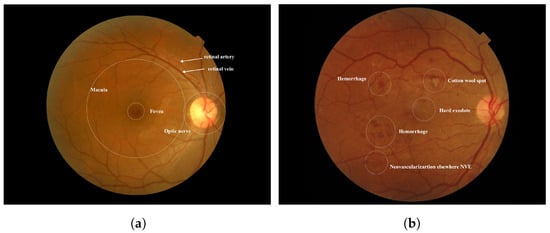

Diabetes occurs when there is an excess of glucose in the blood. This condition can arise if the pancreas does not produce enough insulin, leading to elevated blood sugar levels. High blood sugar can result in serious health complications, including heart disease, kidney disease, nerve damage, and blindness [1]. Diabetic retinopathy (DR) is a severe complication of diabetes that can damage the retina of the eye due to prolonged high blood sugar levels. Throughout the body, diabetes affects blood vessels [2]. In the retina, blockages in small blood vessels can cause fluid to leak or bleed, resulting in eye damage. In response to these blockages, the eyes create new blood vessels; however, these new vessels are often less functional, increasing the risk of bleeding or leakage [3]. Figure 1 illustrates the differences between a healthy retina and one affected by diabetic retinopathy. According to the World Health Organization (WHO), diabetic retinopathy is responsible for approximately 37 million cases of blindness worldwide. Current treatments for DR primarily focus on delaying or preventing further deterioration of vision, highlighting the importance of regular eye screenings with advanced computer systems [4]. Several factors may contribute to low adherence rates for diabetes medications or annual eye examinations. Early diagnosis and treatment of Vision-Threatening Diabetic Retinopathy (VTDR) are crucial to minimizing the risk of vision loss [5].